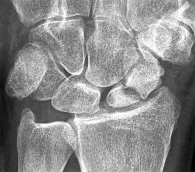

A 24-year-old man sustains a proximal pole scaphoid fracture after a fall on an outstretched hand. He is counseled regarding the high risk of nonunion and avascular necrosis associated with this specific fracture pattern. Which of the following accurately describes the primary blood supply to the proximal pole of the scaphoid?

Correct Answer: Retrograde blood flow from the dorsal carpal branch of the radial artery

Explanation:

The scaphoid receives its primary blood supply from the dorsal carpal branch of the radial artery, which enters the bone distally and provides retrograde blood flow to the proximal pole. This retrograde supply makes proximal pole fractures particularly vulnerable to avascular necrosis and nonunion.